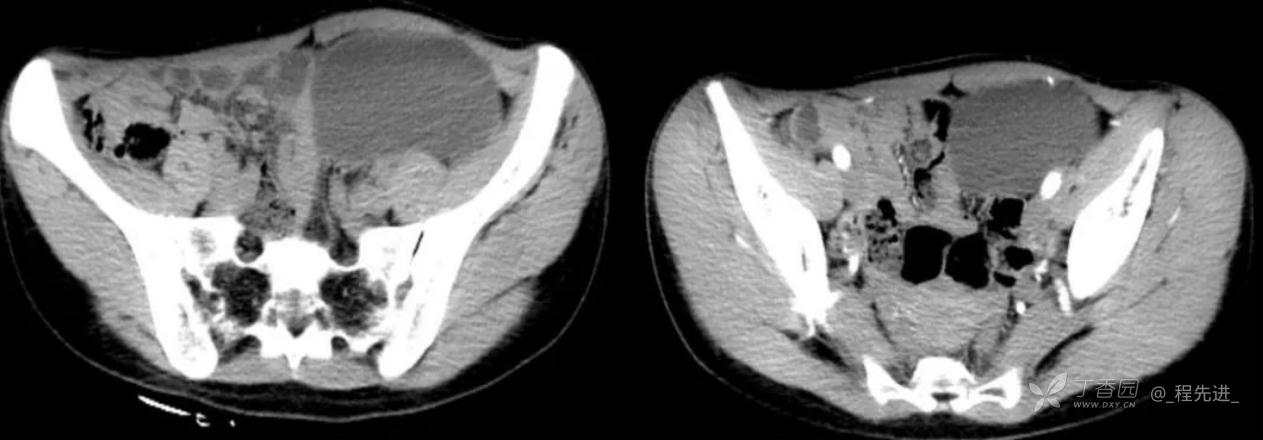

患者性别:女

患者年龄:24岁

主诉:腹痛、发热一天

现病史:一天前无明显诱因出现腹痛并发热不适,伴恶心、干呕,诊所肌注药物(具体用药不详),无缓解,无明显尿频、尿痛。

体格检查:腹肌稍紧张,右上腹部轻压痛,右肾区叩痛